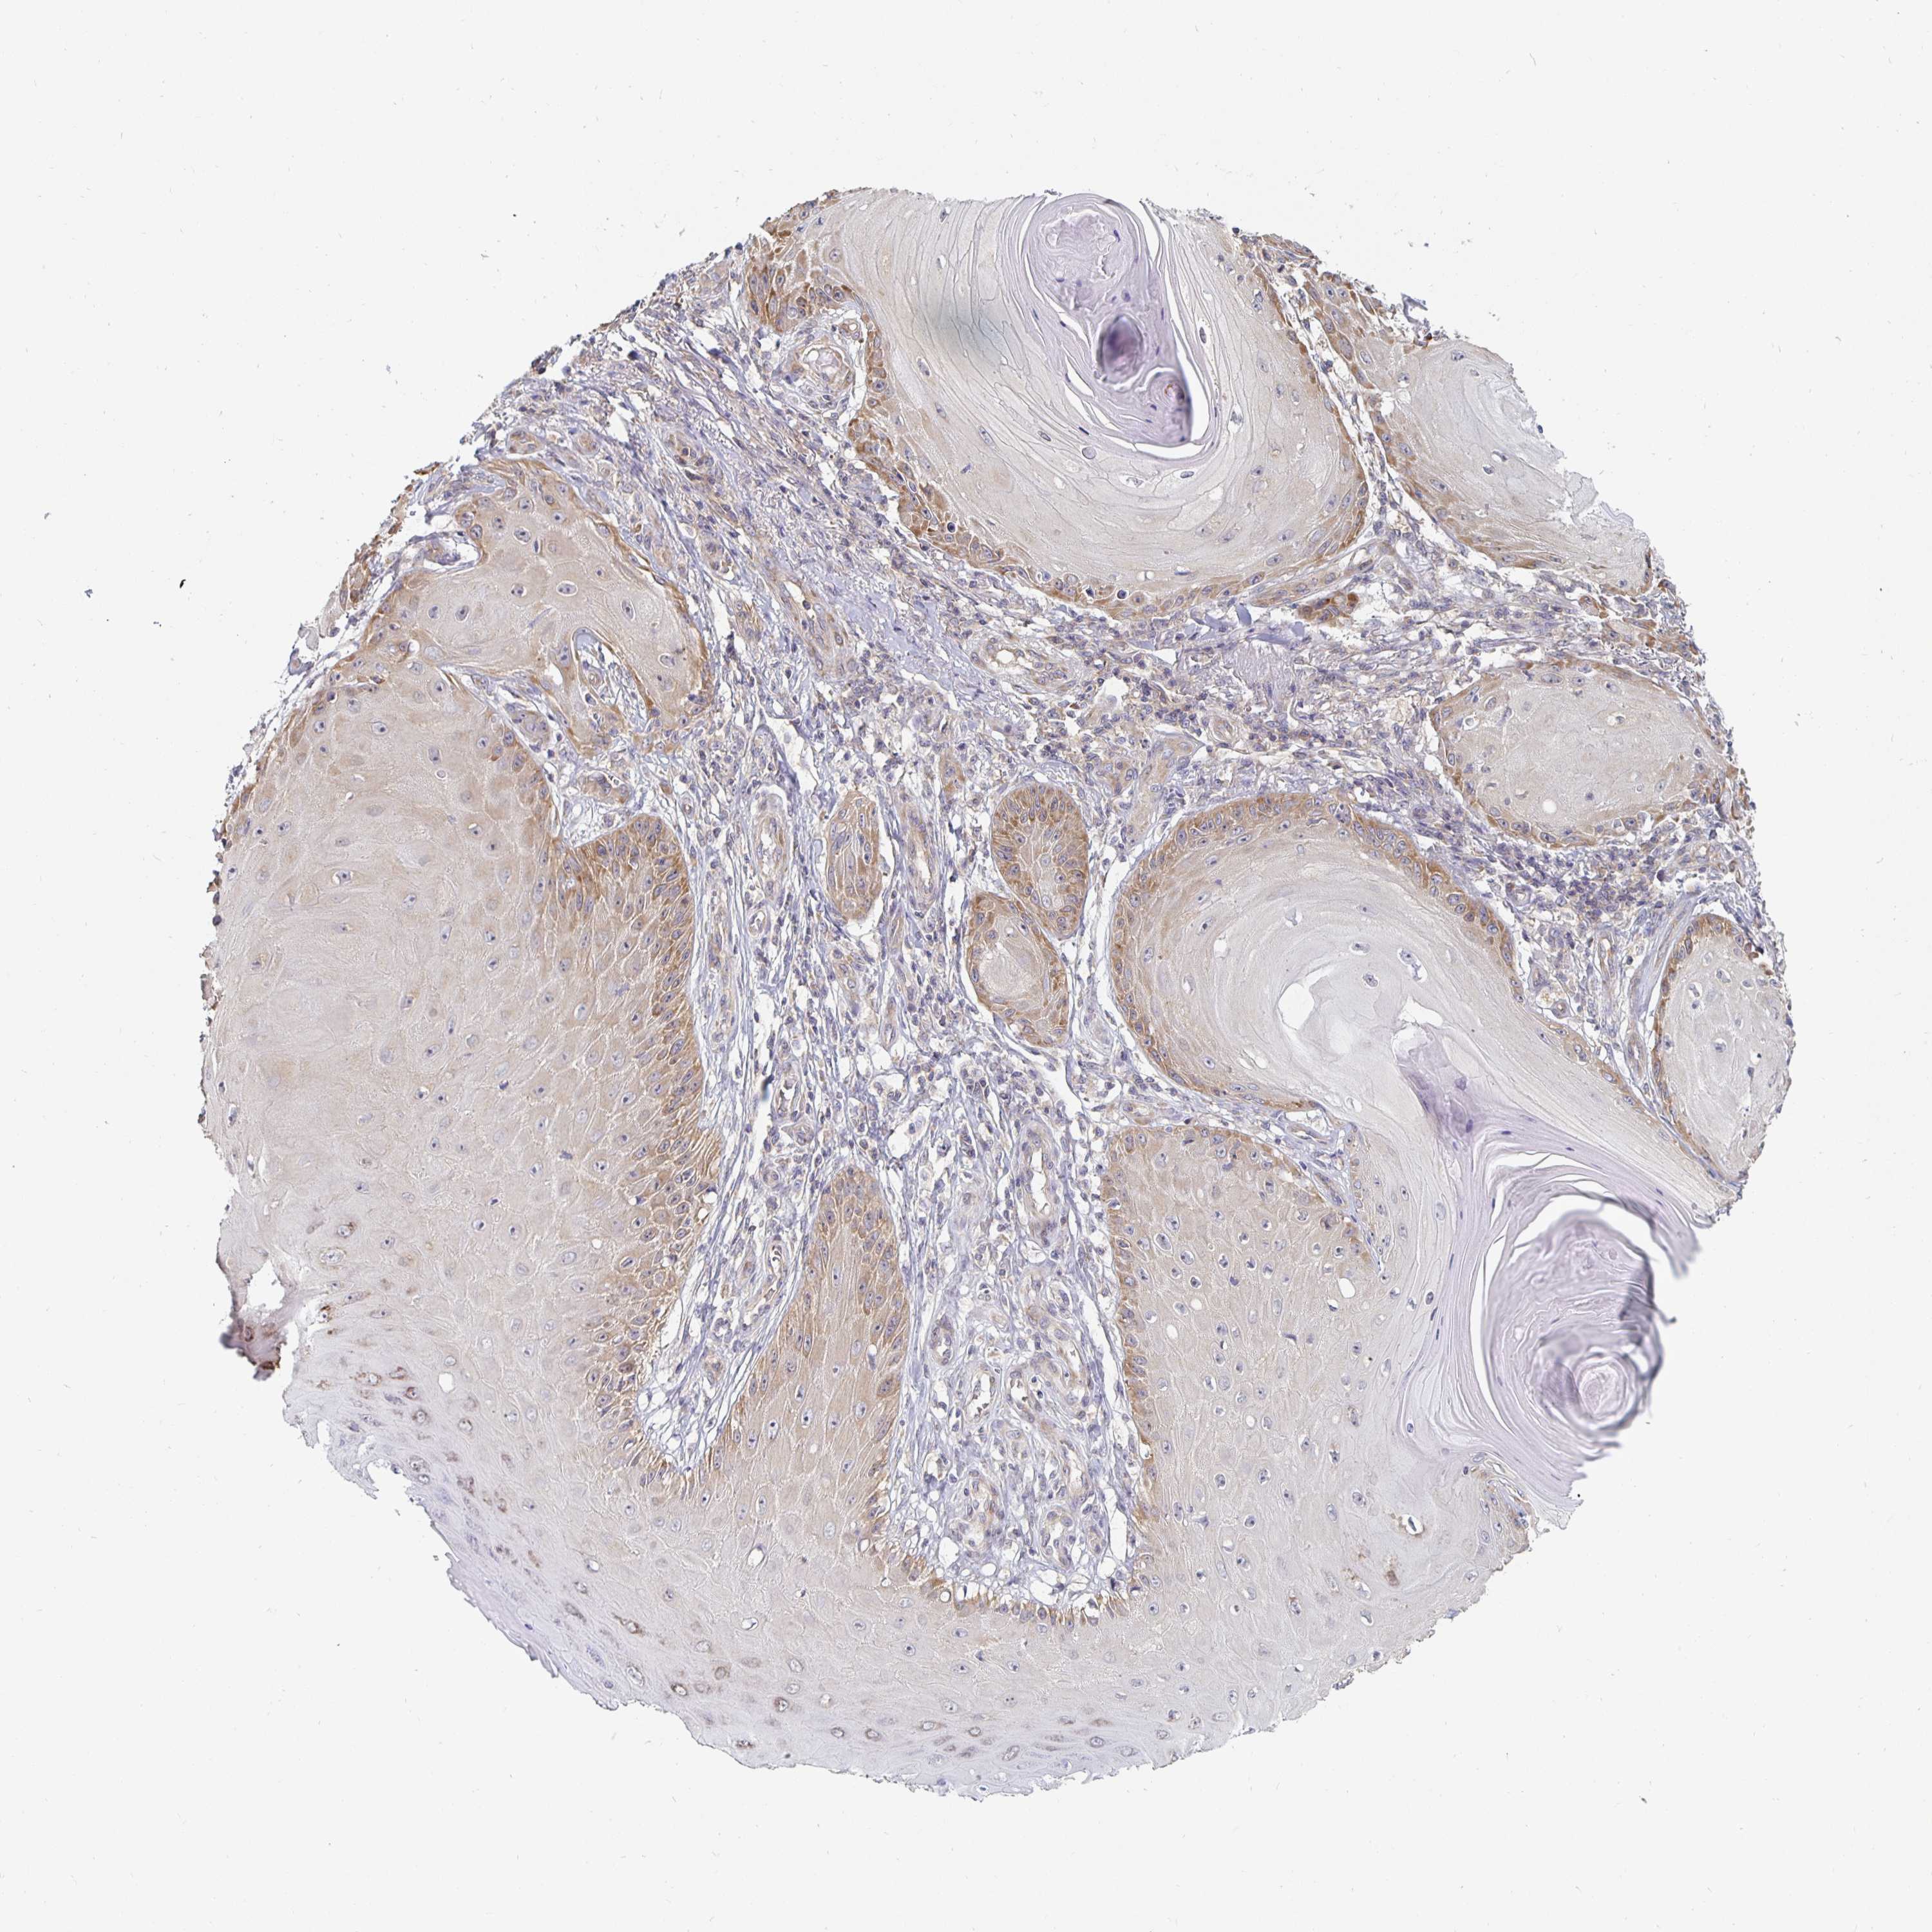

SKIN CANCER - Protein expressioni

A mouse-over function shows sample information and annotation data. Click on an image to view it in a full screen mode. Samples can be filtered based on level of antibody staining by selecting one or several of the following categories: high, medium, low and not detected. The assay and annotation is described here.

Each image is clickable and will lead to virtual microscopy that enables deeper exploration of all samples and also displays staining intensity scores, fraction scores and subcellular localization as well as patient and tissue information for each sample.

Antibody HPA050294

Antibody HPA060836

Antibody CAB021103

Staining

High

Medium

Low

Not detected

Intensity

Strong

Moderate

Weak

Negative

Quantity

>75%

75%-25%

<25%

None

Location

Nuclear

Cytoplasmic/membranous

Cytoplasmic/membranous,nuclear

Basal cell carcinoma

Squamous cell carcinoma, NOS